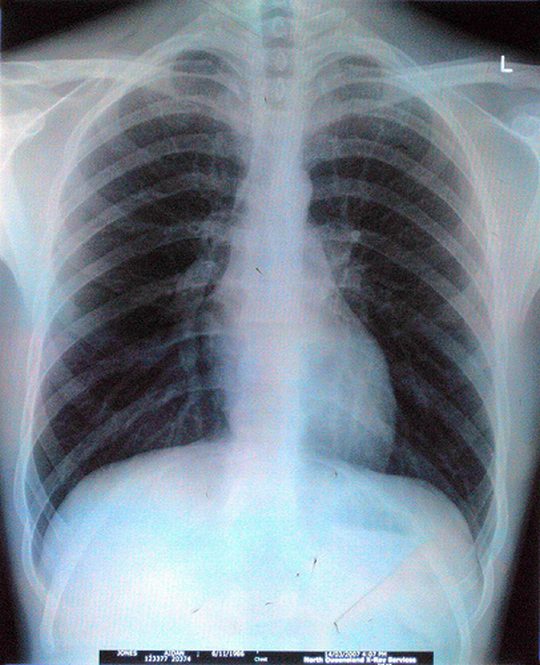

Gruźlica, która wydawała się chorobą zaleczoną, znów jest bardzo groźna Gruźlica, która wydawała się chorobą zaleczoną, znów jest bardzo groźna Aidan Jones / Flickr CC by SA

Gruźlica zabija rocznie 1,7 mln ludzi na świecie. Pilnie potrzeba nowych leków. Ale wielkie koncerny nie są nimi zainteresowane. Indie znalazły na to lekarstwo.